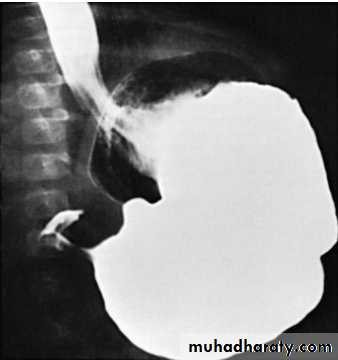

• Contrast studies demonstrate an elongated pyloric channel (string sign), a bulge of the pyloric muscle into the antrum (shoulder sign), and parallel streaks of barium seen in the narrowed channel, producing a “double tract sign”

Barium in the stomach of an infant with projectile vomiting. The attenuated pyloric canal is typical of CHPS.